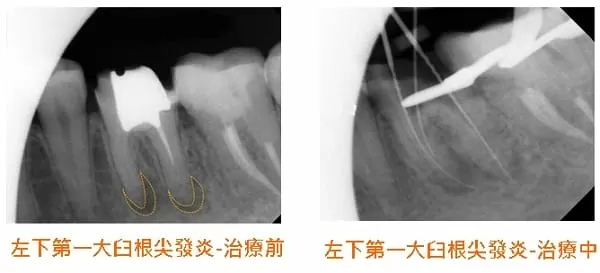

3. 接著進行第一大臼齒的治療;首先,先移除原本的假牙冠,並透由X光片檢查牙根尖發炎狀況,發現近心和遠心牙根尖皆受到感染而呈現慢性發炎。

下圖中可發現,根尖發炎擴散至齒槽骨的狀況,在兩個禮拜內就已獲得有效控制且有改善。